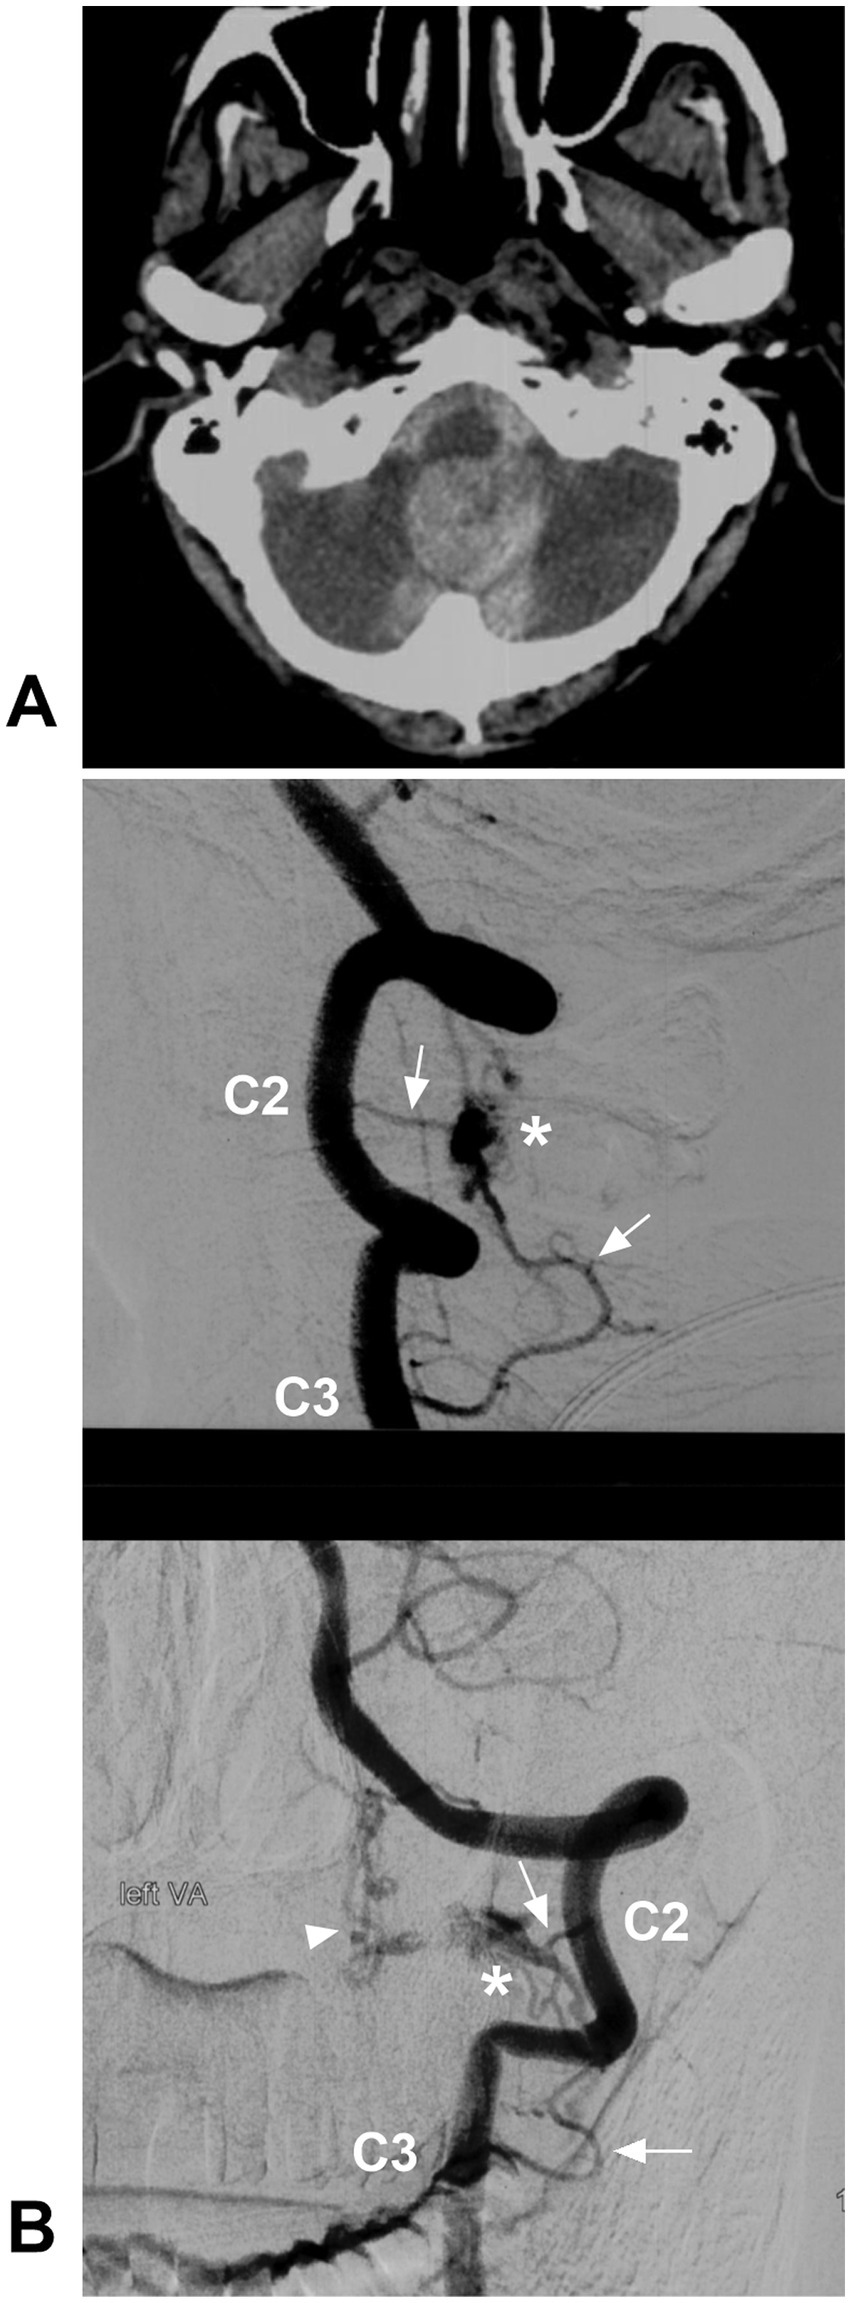

Figure 10

Ruptured CCJ RAVF with upward drainage. (A) CT showing subarachnoid and cisterna magna hemorrhage. (B) Lateral view (upper panel) and anterior posterior view (below panel) DSA of the VA showing an RAVF (asterisks) fed by the C2 and C3 radicular arteries (arrows) and with upward venous drainage (arrowhead in below panel). AVF, arteriovenous fistula; C2 and C3, second and third cervical vertebrae; CCJ, craniocervical junction; CT, computed tomography; DSA, digital subtracted angiography; RAVF, radicular AVF; VA, vertebral artery.